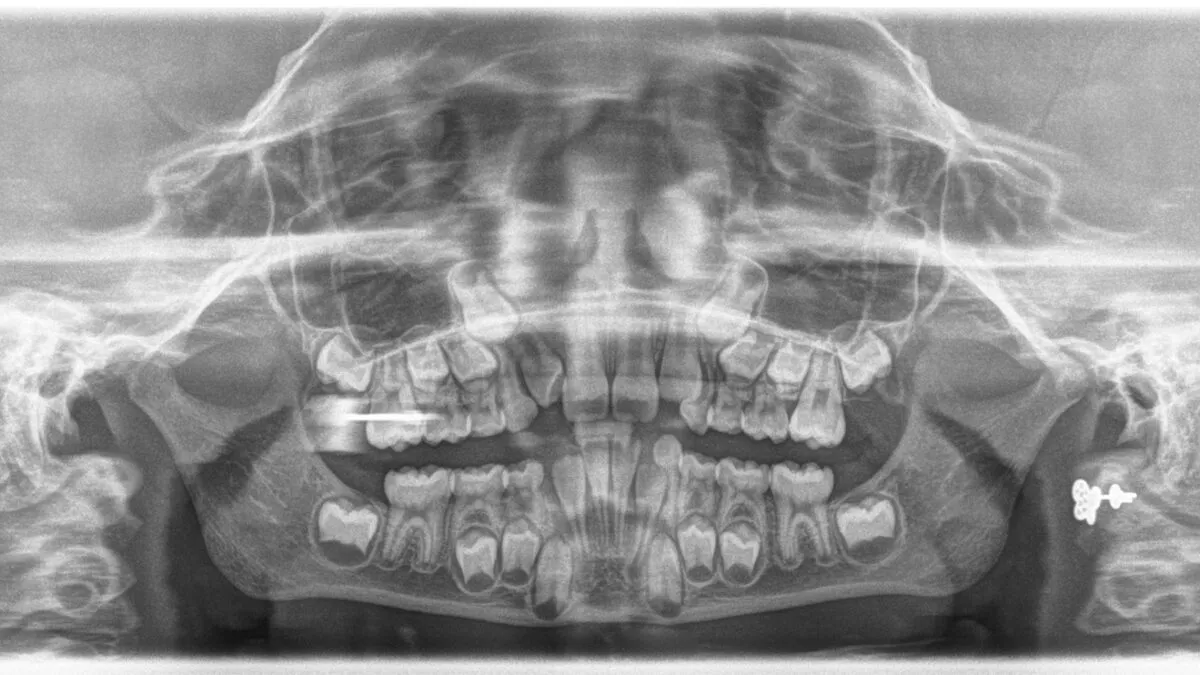

Małe dzieci posiadają komplet 20 zębów mlecznych 10 w szczęce i 10 w żuchwie. W ich skład wchodzi 8 siekaczy, 4 kły oraz 8 zębów trzonowych. Co ciekawe, w uzębieniu mlecznym nie występują zęby przedtrzonowe, co jest jedną z kluczowych różnic w porównaniu do uzębienia stałego.

U dorosłego człowieka liczba zębów stałych waha się zazwyczaj od 28 do 32. Pełny zestaw 32 zębów stałych obejmuje wszystkie zęby mądrości (ósemki). Jednakże, jeśli zęby mądrości nie wyrzynają się lub zostają usunięte, standardem dla wielu osób jest posiadanie 28 zębów stałych.

Zęby mądrości, potocznie nazywane ósemkami, są główną przyczyną zmienności w liczbie zębów stałych u dorosłych. Wiele osób nigdy ich nie ma, u innych wyrzynają się tylko częściowo, a u jeszcze innych są usuwane ze względów ortodontycznych lub chirurgicznych. Z tego powodu posiadanie 28 zębów stałych jest bardzo powszechne i w pełni funkcjonalne.

Jak już wspomniałam, dzieci mają 20 zębów mlecznych, w tym 8 siekaczy, 4 kły i 8 zębów trzonowych. Pełnią one kluczowe role w życiu dziecka: umożliwiają gryzienie i żucie pokarmu, co jest niezbędne dla prawidłowego trawienia. Są również fundamentalne dla prawidłowego rozwoju mowy i artykulacji dźwięków. Co więcej, zęby mleczne działają jak naturalne "szablony", utrzymując przestrzeń dla zębów stałych, które dopiero się rozwijają. Warto również zwrócić uwagę na różnice między zębami mlecznymi a stałymi:

Wymiana uzębienia z mlecznego na stałe to proces, który rozpoczyna się zazwyczaj około 6. roku życia dziecka. Jest to moment, kiedy wielu rodziców zauważa pierwszy wypadający ząbek. Cały ten proces trwa dość długo, bo aż do około 12-13. roku życia, kiedy to większość zębów mlecznych zostaje zastąpiona przez stałe odpowiedniki.

Okres, w którym w jamie ustnej dziecka obecne są zarówno zęby mleczne, jak i stałe, nazywamy uzębieniem mieszanym. To etap przejściowy, który jest niezwykle ważny dla prawidłowego rozwoju zgryzu. W tym czasie stomatolog lub ortodonta może ocenić, czy zęby stałe wyrzynają się prawidłowo i czy jest wystarczająco miejsca w łuku zębowym. Regularne kontrole są kluczowe, aby w porę wychwycić ewentualne nieprawidłowości i zapewnić dziecku zdrowy i piękny uśmiech w przyszłości.

Jeśli podejrzewasz u siebie lub u swojego dziecka nietypową liczbę zębów czy to braki, czy zęby nadliczbowe koniecznie skonsultuj się ze stomatologiem lub ortodontą. Tylko profesjonalna diagnoza, często wsparta badaniem rentgenowskim, pozwoli na dokładne określenie problemu i opracowanie odpowiedniego planu leczenia. Wczesna interwencja jest kluczowa, aby zapobiec poważniejszym problemom w przyszłości i zapewnić zdrowy, funkcjonalny uśmiech.